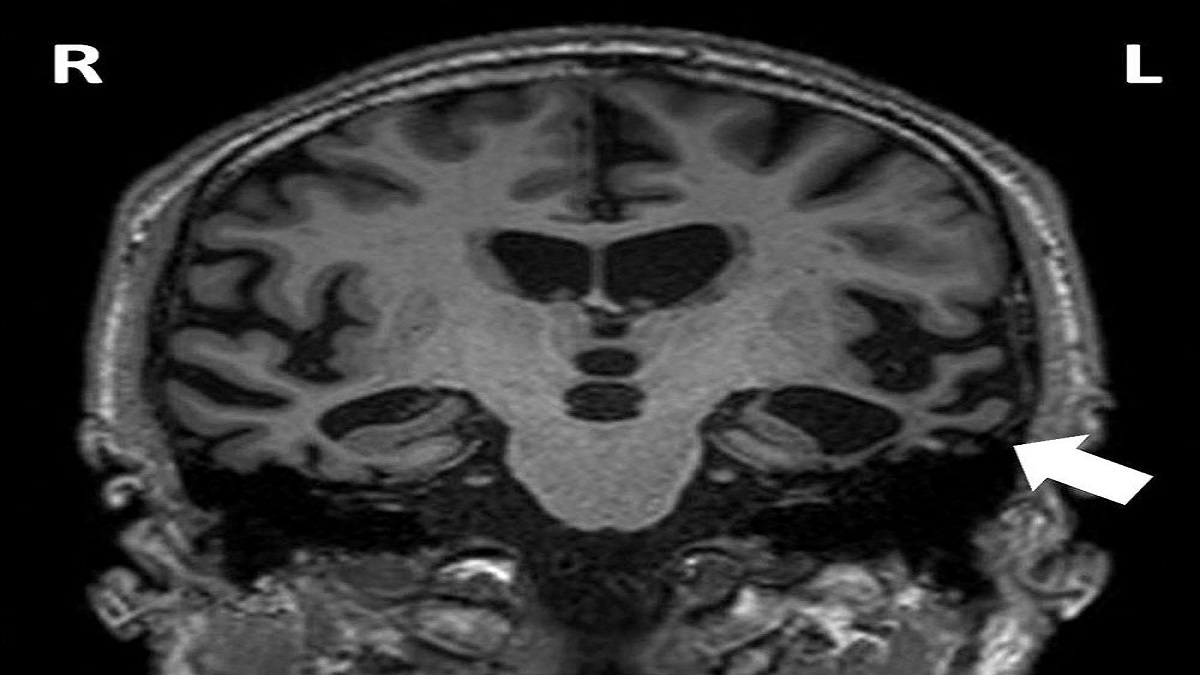

أكد أطباء في مركز الصحة بألمانيا أن حاجز الدم في الدماغ هو الحاجز الفسيولوجي بين المساحات السائلة في مجرى الدم والجهاز العصبي المركزي.

وأشاروا إلى أن وظيفة حاجز الدم في الدماغ تتمثل في منع السموم ومسببات الأمراض من الوصول إلى الدماغ من الدم.

وإذا لم يعمل هذا الحاجز بشكل صحيح، فإن الجسم يصبح عُرضة للأمراض مثل ألزهايمر والتصلب المتعدد.

وأضاف المركز أنه يمكن حماية حاجز الدم في الدماغ من خلال التغذية الصحية، أي تناول الأغذية المهمة لوظائف المخ مثل الأغذية الغنية بالأحماض الدهنية أوميجا 3 (الأسماك والمكسرات) والمغنيسيوم (الموز والمكسرات والكاكاو وبذور القرع العسلي) وفيتامين B12 (لحوم وكبد البقر والبيض ومنتجات الألبان والأسماك).